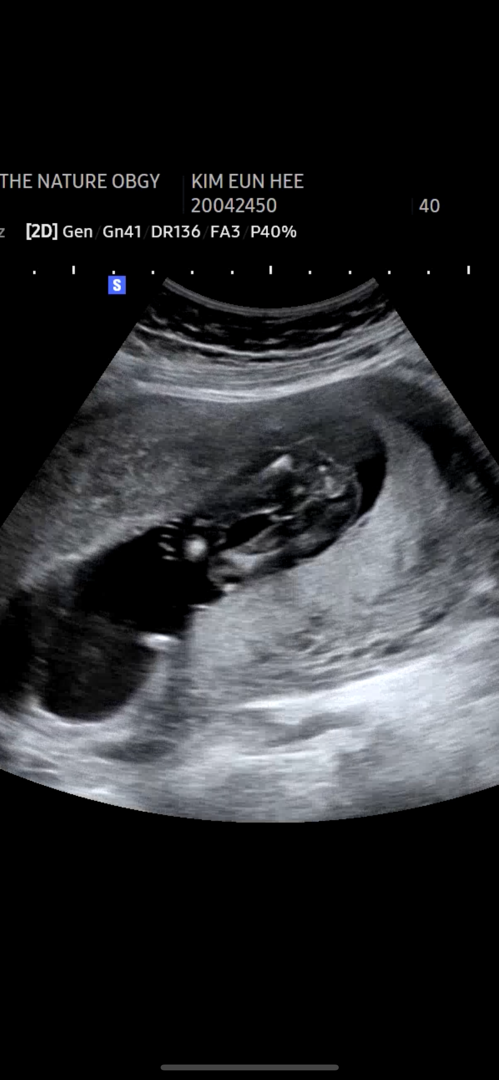

성별이 뭘까요 ㅠ

선생님은 처음에 공주님이라고 하셨다가 아이가 다리를 붙이고 있어서 또 다음에 봐야할거 같다고 하시는데 ㅠ 그나마 선명해졌을때 캡쳐해서보는데 가운데 튀어나온거같기도하고 ..

16주차입니다!

그럼 아들 같아요!